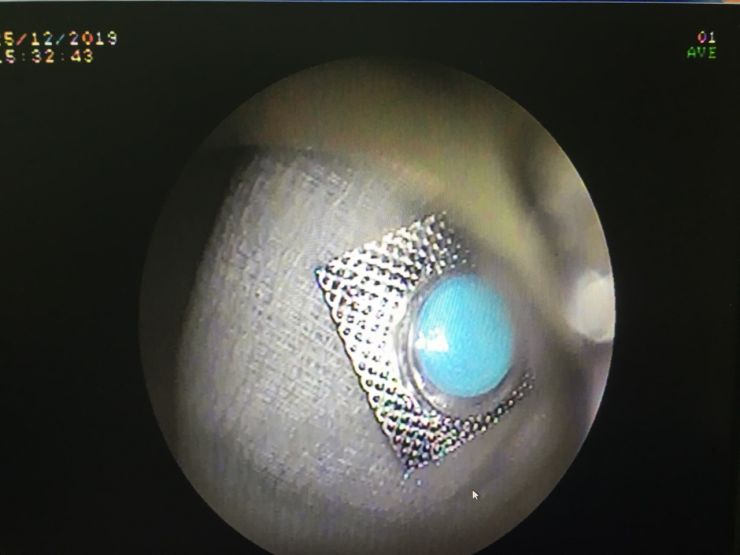

Chiều ngày hôm trước, bệnh nhân vào Khoa Cấp cứu trong tình trạng đau tức ngực sau xương ức do nuốt phải vỏ thuốc còn nguyên vỏ. Sau đó, bệnh nhân được chuyển vào phòng Nội soi để tiến hành nội soi, chẩn đoán cho thấy dị vật viên thuốc còn nguyên vỏ kích thước 9 x 9mm, hình vuông cạnh sắc bén như dao ở thực quản đoạn giữa, có nguy cơ gây thủng thực quản vào trung thất có thể dẫn đến tử vong.

Để tránh nguy cơ viên thuốc sặc vào phổi, Đơn vị Nội soi mời bác sĩ Khoa Gây mê hồi sức tiến hành tiền mê để nội soi gắp dị vật an toàn cho bệnh nhân. Do dị vật sắc bén nên ê kíp bác sĩ phải dùng chụp dị vật bằng silicon để bao dị vật tránh chảy máu và thủng thực quản khi kéo dị vật ra ngoài.